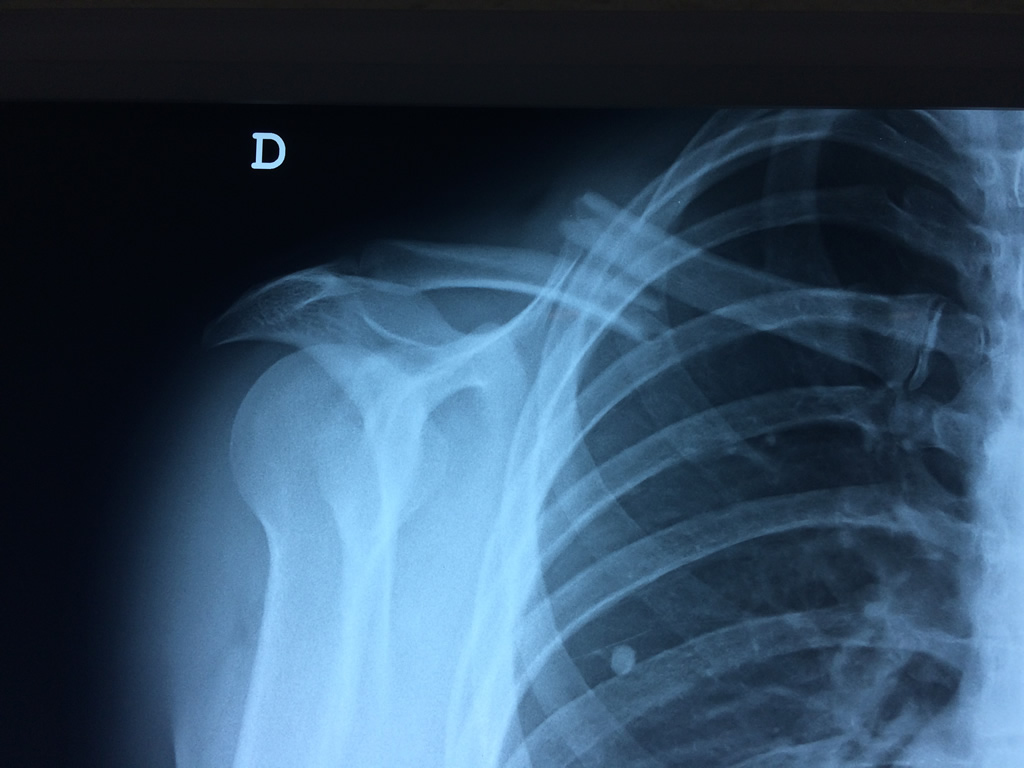

La clavícula es un hueso largo, con forma de "S" itálica, situado en la parte anterosuperior del tórax. Junto con la escápula forman la cintura escapular. Se puede palpar por toda su longitud y se extiende del esternón al acromion de la escápula, siguiendo una dirección oblicua lateral y posterior.